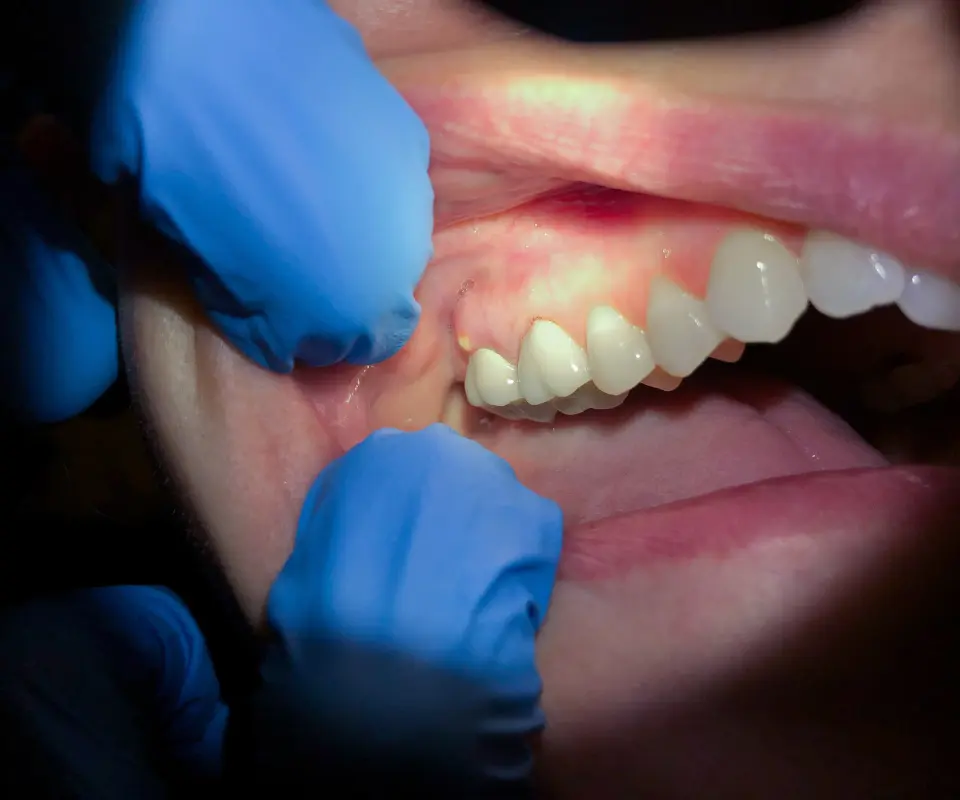

Can gum disease cause my jaw to swell?

Yes. Advanced gum disease (periodontitis) can lead to infection and inflammation that spreads to the jawbone and surrounding tissues. Maintaining your oral health with regular cleanings, brushing and flossing, and professional checkups is crucial to prevent this.